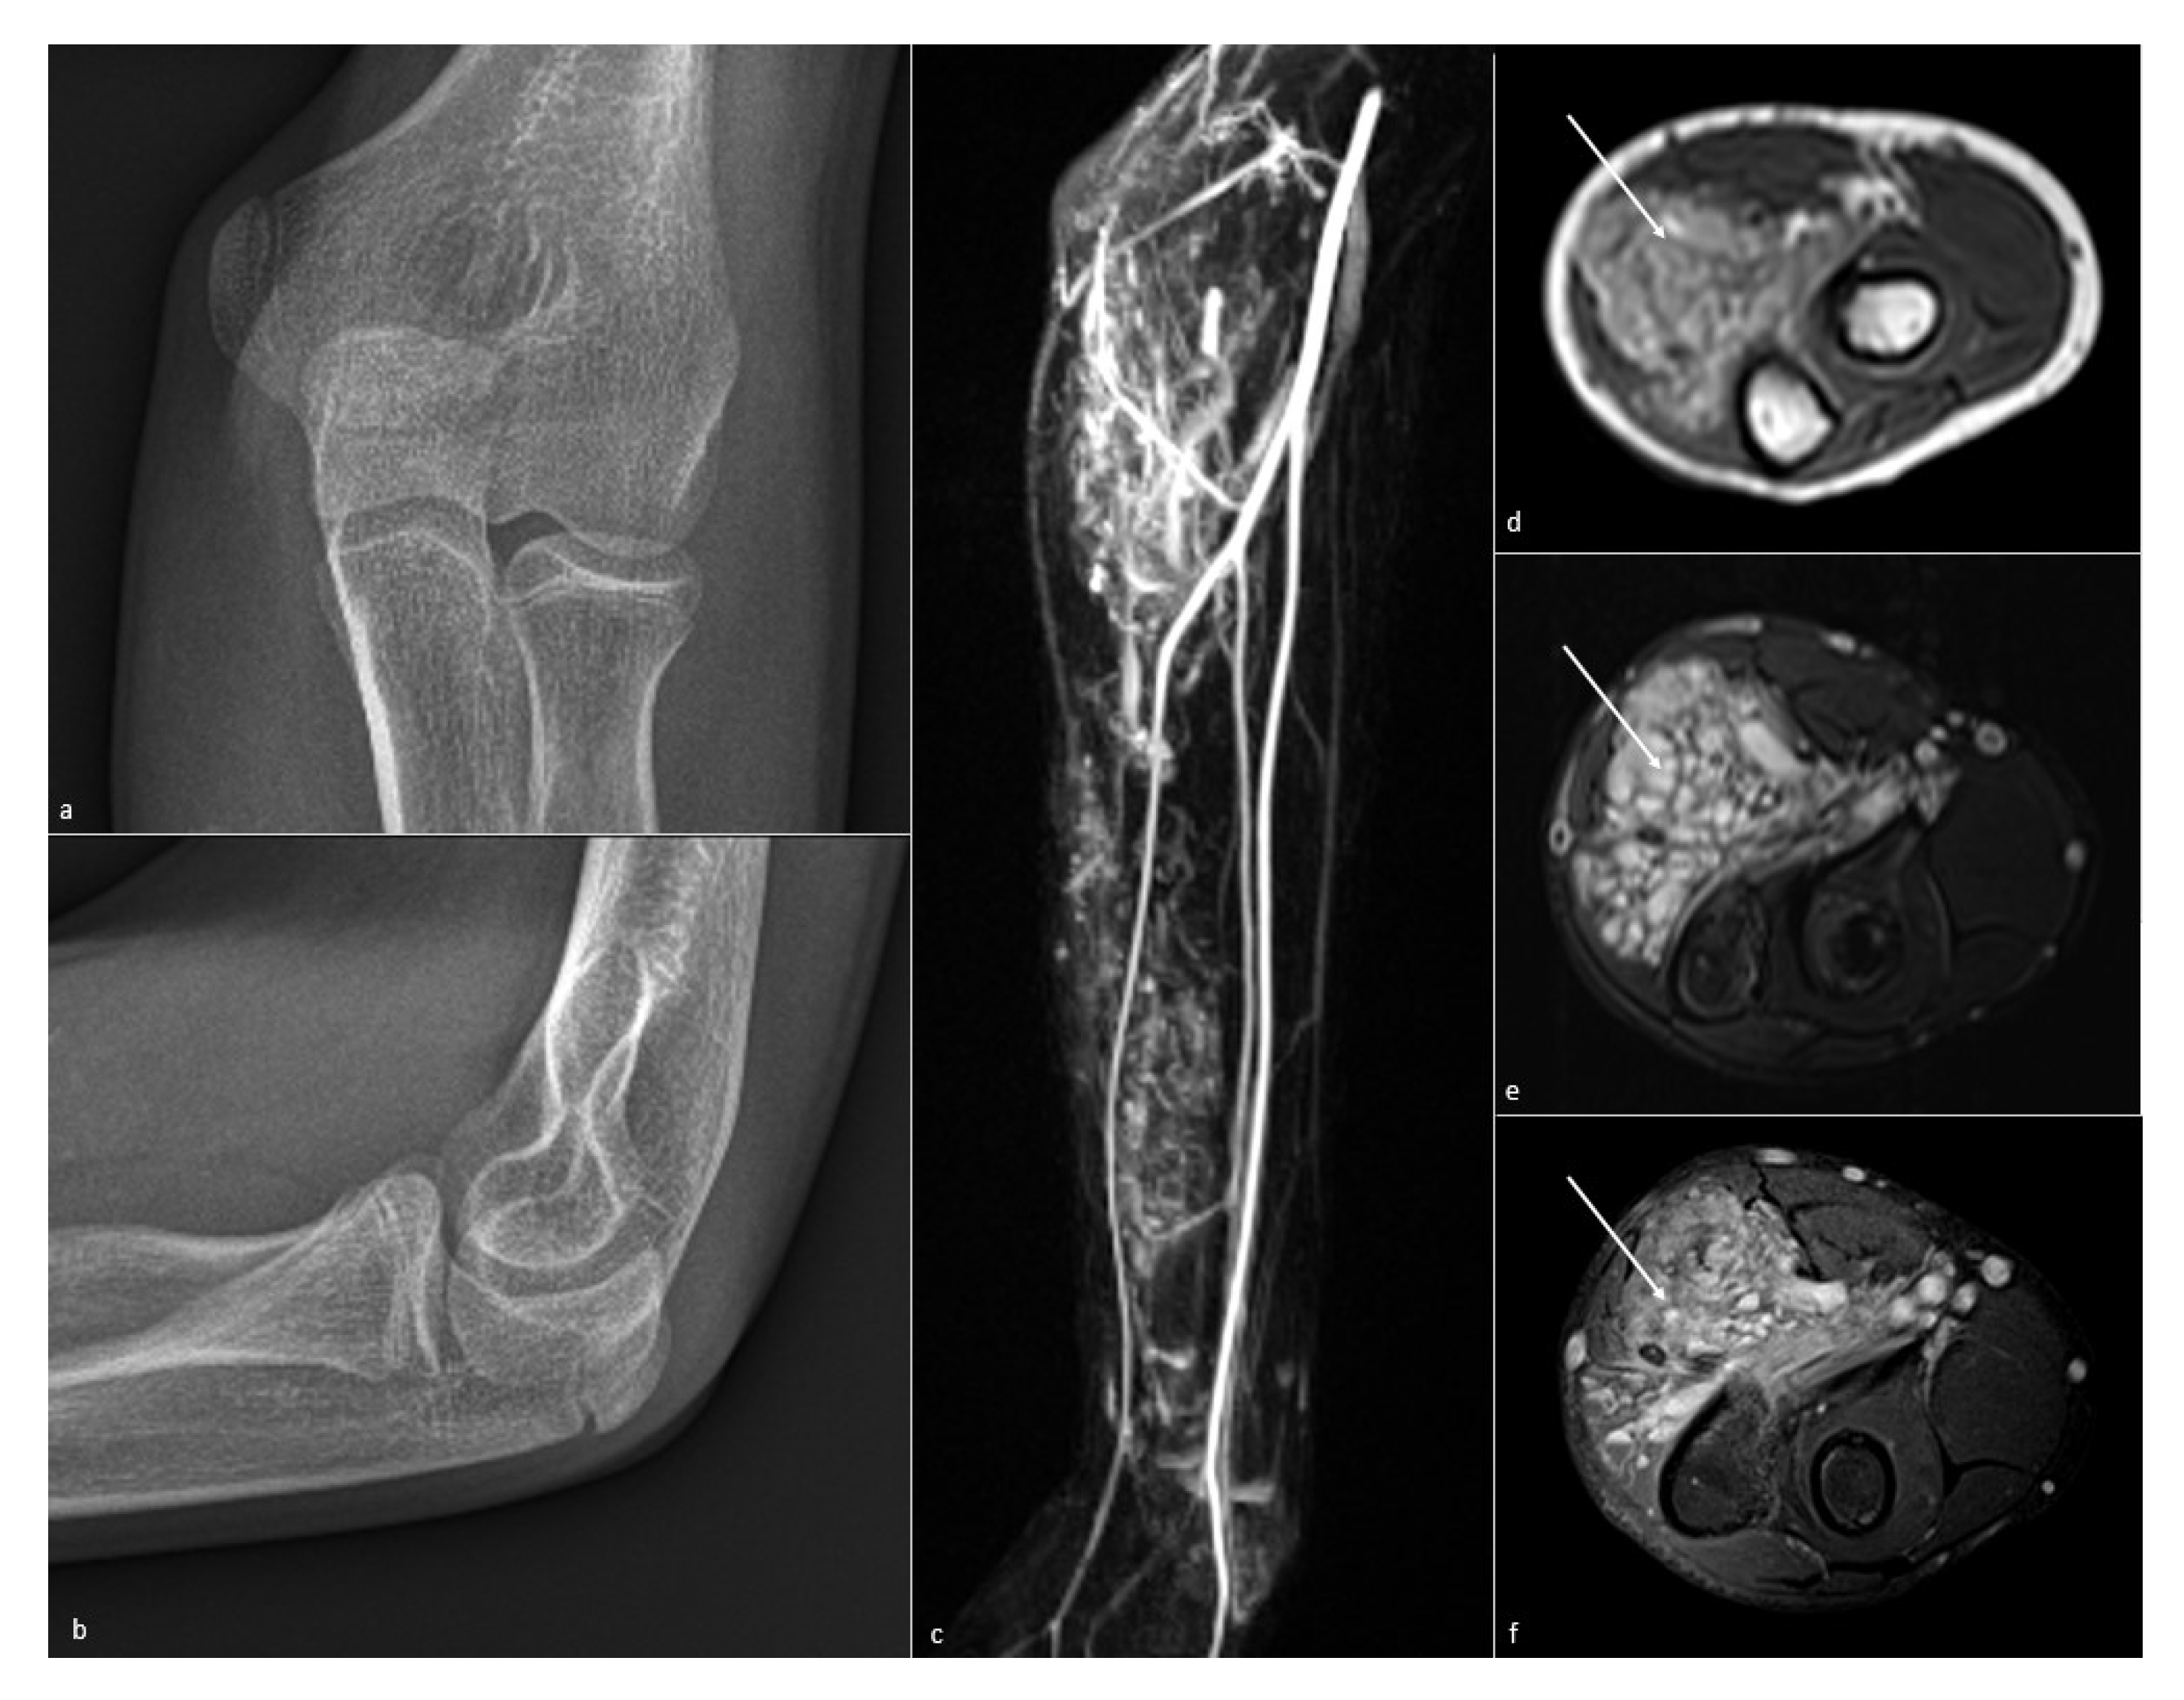

5.4. MR Imaging

5.5. Dynamic and Kinematic CT